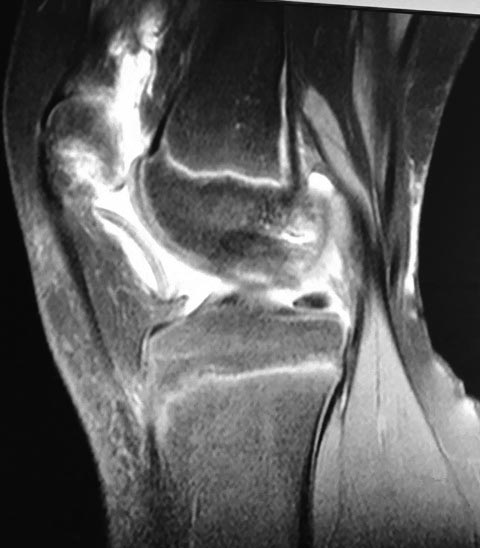

Девочка 10 лет. Травма 1 месяц назад упала на горке. Лечилась

консервативно. По данным МРТ имеется остеохондральный дефект наружного

мыщелка бедренной кости и свободный костно-хрящевой фрагмент размером 3

см. в диаметре. План лечения: артротомия, рефиксация по возможности. На